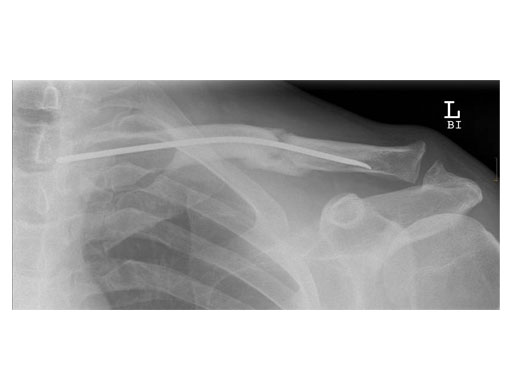

Case 1: Male, 56 years, Bicycle accident

Case 2: 51 years, male, hit by tree